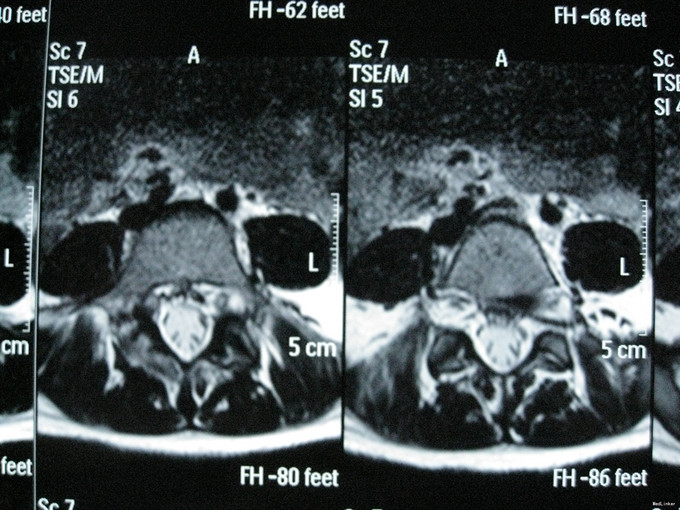

腰椎峡部裂

主诉:诉反复腰痛1年余,加重1月。 病史:患者1年前无明显诱因出现腰部疼痛,性质为胀痛,活动后疼痛加剧,平卧休息可缓解,无向双下肢放射,无伴间歇性跛行,无双下肢麻木。自服药物治疗(具体不详)。近1月来腰部疼痛反复出现。现为进一步诊治收入我科。患者起病以来,无发热,无胸闷气促,无咳嗽咳痰,无腹胀腹痛,无尿频尿急。精神、食欲、睡眠尚可,大小便正常,体重无明显下降。

查体:腰椎无畸形,生理弯曲存在,有棘突台阶感,腰椎活动受限。L5棘突间及棘突旁压痛(+)、叩痛(+)。双下肢肌力感觉正常。双侧直腿抬高试验(-),加强试验(-)。双侧膝反射、踝反射对称可引出。髌、踝阵挛(-)。双侧Babinski征(-)。

诊断:腰5峡部裂滑脱 治疗:给予行后路峡部裂滑脱复位并峡部裂植骨椎板钩固定融合术。

随访3个月,患者腰痛消失,恢复满意。复查x光示峡部透亮带消失,植骨融合效果满意。 讨论: 峡部裂行椎板钩固定融合,可简化手术操作,减小创伤。是有效的治疗方式之一。